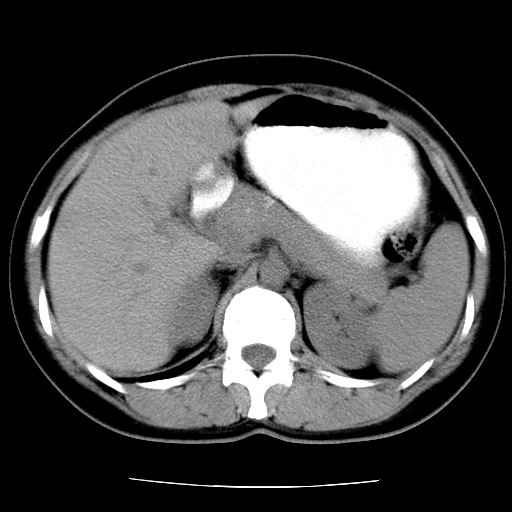

标题: CT16892:女40Y,急性阑尾住院!

女40y,急性阑尾住院!术前发现请会诊!

考虑门静脉瘤样扩张可能,建议增强扫描

胰头假性囊肿也有可能,建议增强

病灶位于门静脉的位置 ,有层面显示血管夹层样改变 ,考虑是门静脉瘤样病变1

病灶位于门静脉的位置 ,有层面显示血管夹层样改变 ,考虑是门静脉瘤样病变,建议进一步增强ct检查。

肝胃间隙良性占位病变,考虑囊肿可能性,不除外神经源性肿瘤,建议增强

肝门区囊性占位,壁有钙化,考虑良性。来源难定。